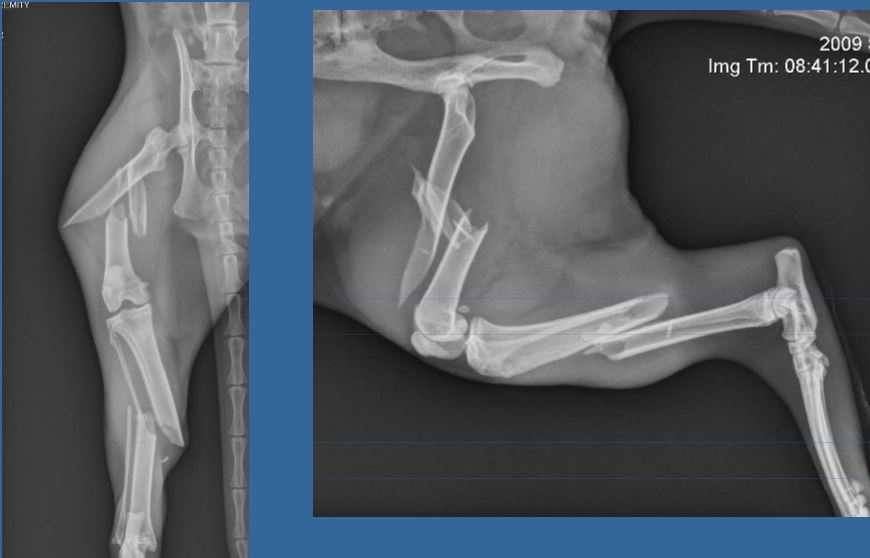

5

Q

1 year old DSH, 4.5kg

HBC 24 hours ago.

Classify and assess fracture, and give repair options

A

Severely comminuted femoral fracture

and

Short oblique tibial fracture

Fx score= 5

Repair: 2 ESFs (Type 1A), on femur + cerclage wire and IM pin